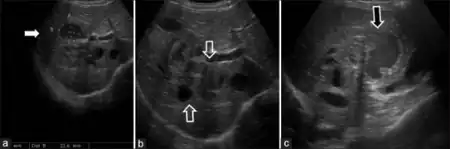

a-c)Sonography images of male child diagnosed with hepatic visceral larva migrans

Signs and Symptoms are consistent with fever, hepatomegaly, leucocytosis, coughing [7]